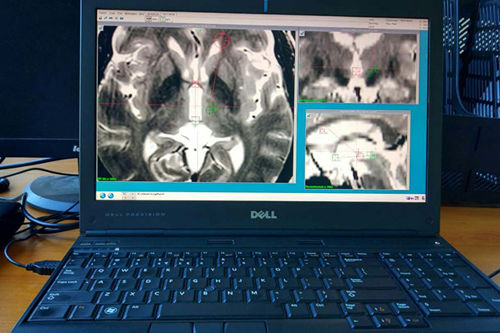

在为患者做立体定向手术

应用我院高端精密的LEKSELL脑立体定向仪和先进的手术计划系统,为王先生制定了详细的手术计划,在局麻下行“立体定向左侧vim核毁损术”,手术过程顺利,术中肢体震颤立即消失,治疗效果显著,解决了困扰王先生十年的痛苦,王先生及家人对手术治疗很满意。

应用先进的手术计划系统:计算可精准到0.1毫米的手术靶点,路径及入颅点

立体定向神经外科手术(简称脑立体定向术),在患者头部安装立体定向仪,行核磁检查,应用计算机技术及其软件,把影像学资料传输至手术计划系统,进行图像的三维重建,可直观显示大脑的解剖结构,计算出手术靶点的精准坐标值,再输入立体定向仪后进行精准手术。同时可设计手术穿刺路径,计算病变大小和范围,使手术个体化,到达更精准、更安全、更有效、直观、省时、创伤小的目的。目前在世界范围应用日益广泛,分为二大类:1、脑深部核团电刺激术或叫脑起博器(DBS)术。2,脑深部核团切开术。